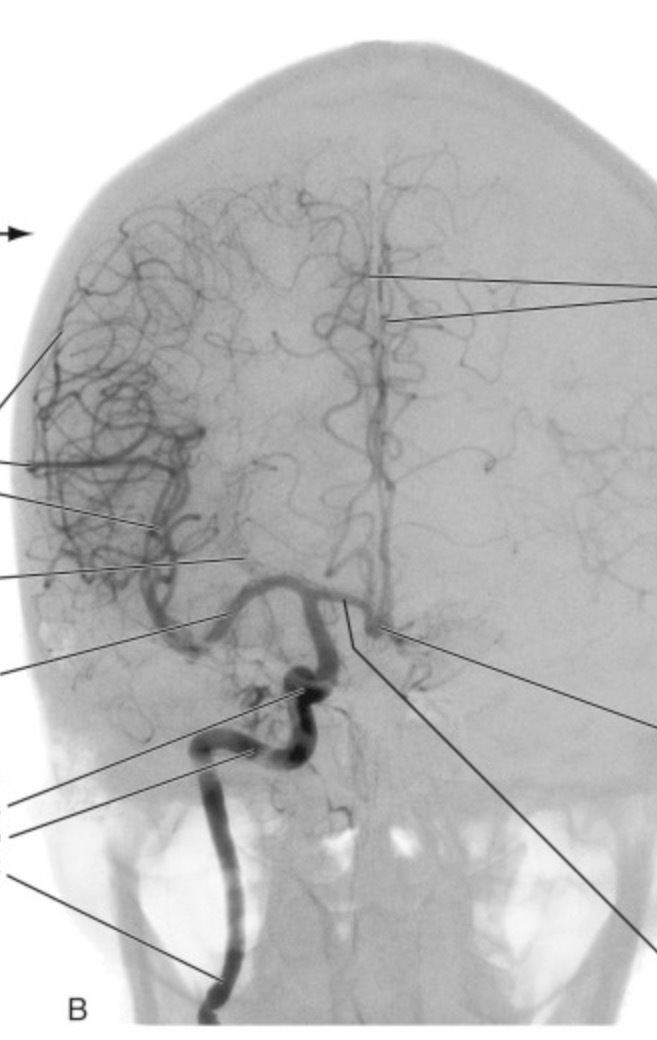

middle cerebral artery

– 2. What area of the brain does it supply?

– 3. What does this part of the brain do?

– 4. How will the patient present if these areas are damaged?

The majority of the hemisphere!